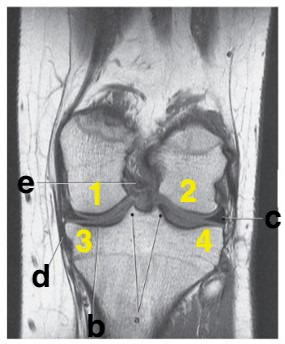

Medial meniscus

posterior cruciate ligament

Which letter is pointing to the posterior cruciate ligament?

e

medial collateral ligament

Which letter is pointing to the anterior cruciate ligament?

c

Where is the tibial plateau?

3 and 4